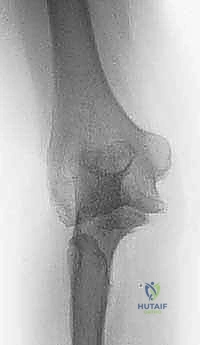

FIG 2 • AP and lateral radiographs of the elbow in a patient with posttraumatic arthritis of the elbow.